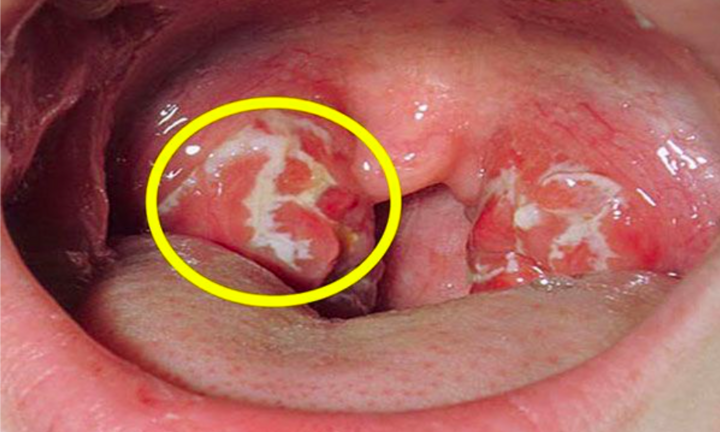

Ung thư vòm họng: Triệu chứng sớm nhất là gì, cách điều trị ra sao?

Đây là những triệu chứng điển hình của bệnh ung thư vòm họng, nếu nghi ngờ, bạn cần phải đi khám càng sớm càng tốt.